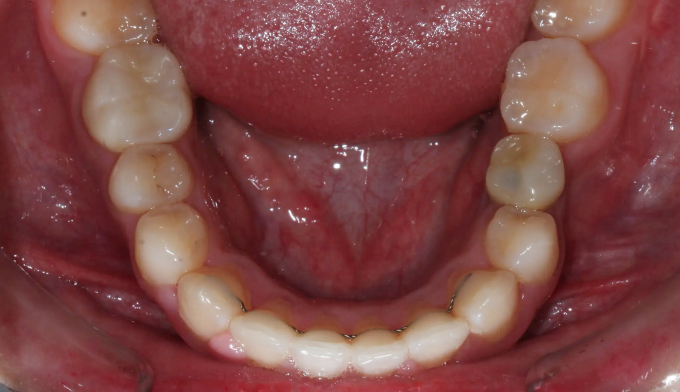

돌출입과 불규칙한 앞니를 가지고 있습니다. 그리고 아래쪽에 ‘임플란트’가 있습니다.

후방이동이 불가하므로 악궁확장을 통하여 공간확보를 시도하였고, 동시에 돌출감도 해소되었습니다.

최종적으로 임플란트의 존재때문에 중심선을 맞추지는 못했으나 환자분은 너무 만족해하셨습니다.

총 치료기간은 14개월 소요되었습니다.